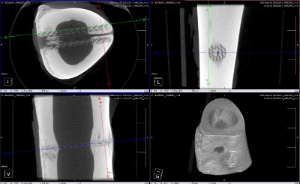

- Insights and clinical evidence from a recent animal study evaluating osseointegration with porous HA-enhanced PEEK

- Implications for future clinical applications and device design